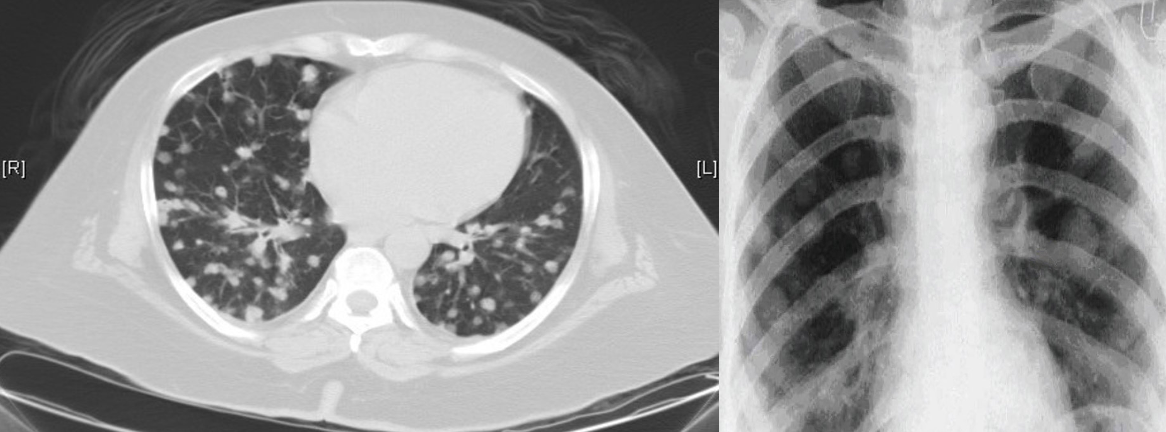

CT chest (axial plane; lung window) of a patient with lung metastases from colon carcinoma *Multiple small, circumscribed nodules of varying sizes can be seen in both lungs.

X-ray chest (PA view) of a patient with lung metastases Multiple pulmonary nodules w/ circumscribed margins can be seen in both lungs*